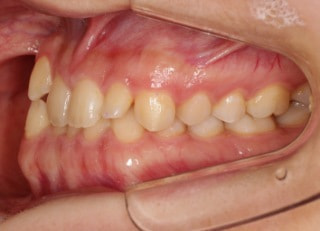

治療開始から25ヶ月後